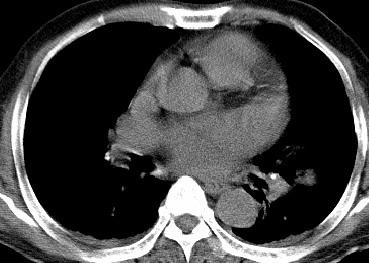

以下是引用光影相伴在2008-4-20 14:39:00的发言:[br]支持:1)左侧中央型肺癌伴左肺上叶阻塞性肺炎。、[br] 2)双侧少量胸腔积液。

以下是引用xianxianzhongyi在2008-4-20 14:44:00的发言:[br]本人愚见:次病例短短两月的时间,呈现如此大面积实变,病变增长过于迅速,此其一。其二,病变在动脉早期既有明显强化。其三,左上叶后段及下叶背段多叶受累。其四,肺门及纵隔内未见明显肿大的淋巴结。估计层面较厚段支气管显示不清。 诊断:炎性实变可能性大。